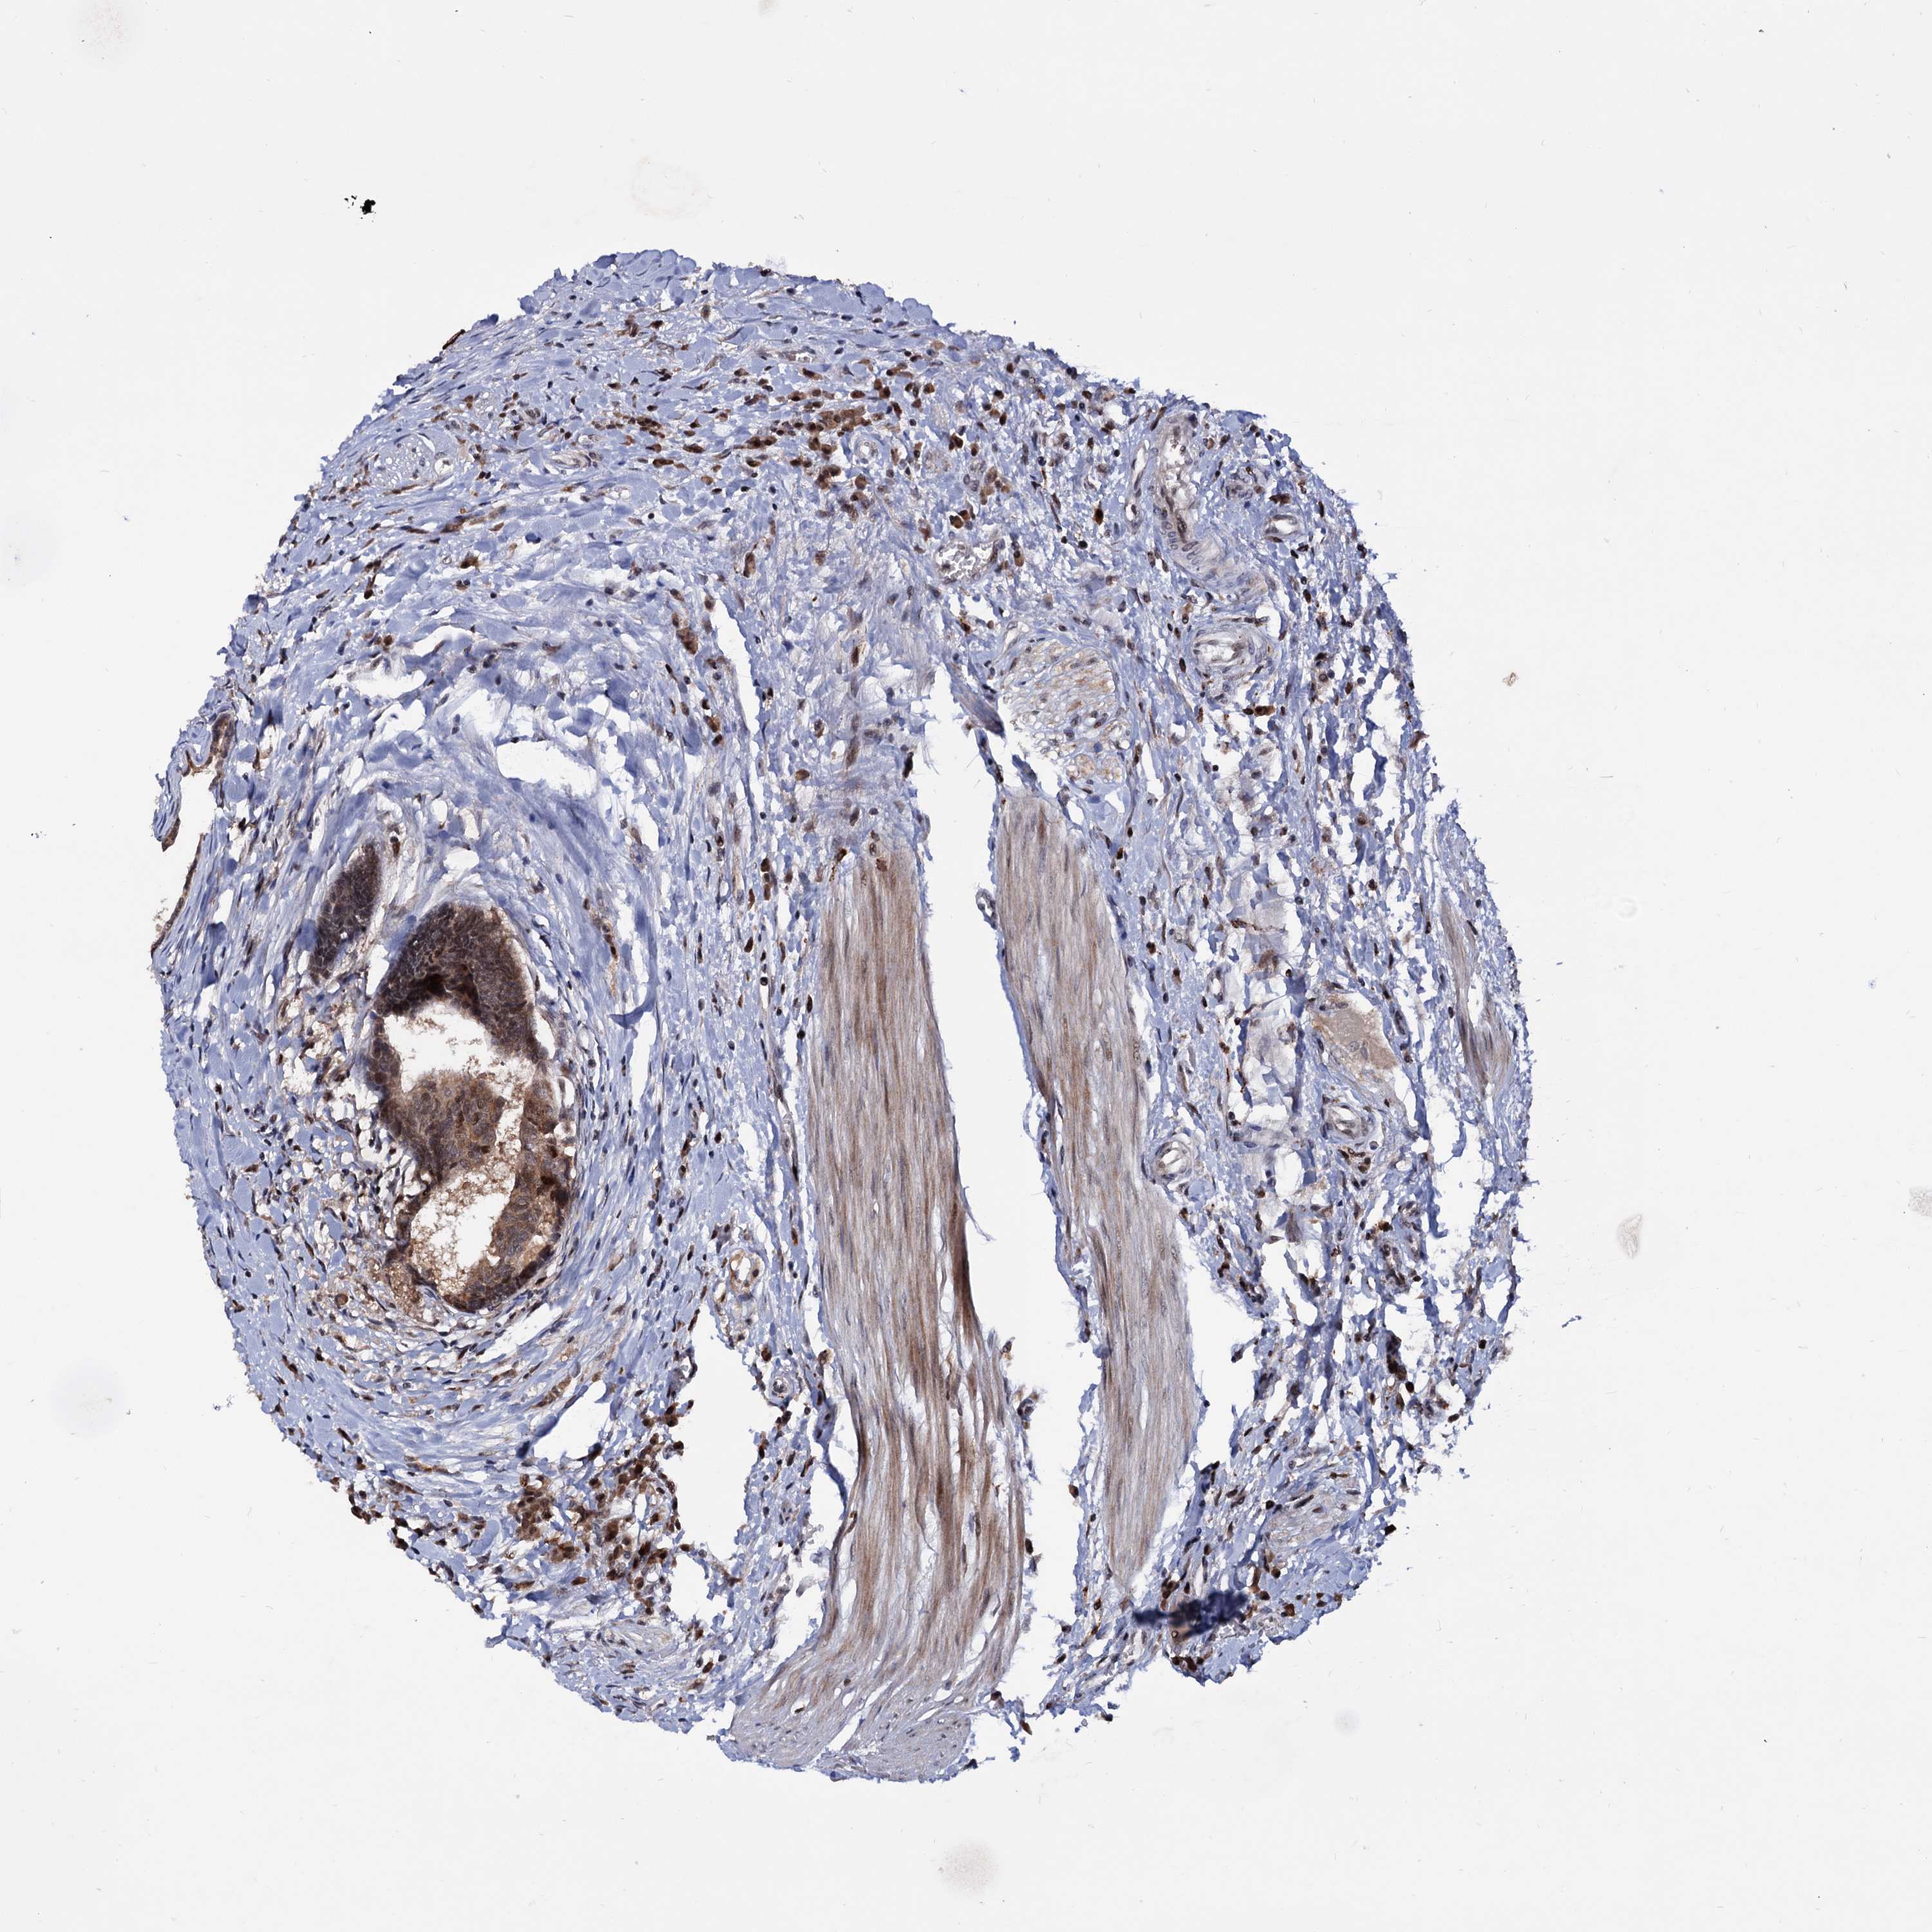

CANCER COLORECTAL CANCER Show tissue menu

Colorectal cancer

Colon adenocarcinoma